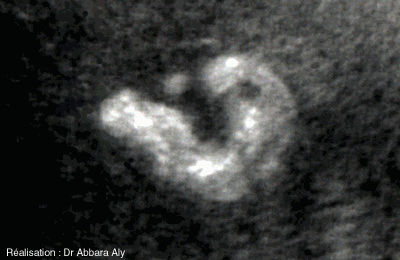

Pavillon de l'oreille externe - foetus de 36,5 SA - Imagerie vidéo récente Coupe frontale passant par l'oreille externe comparaison entre pavillon normal et pavillon d'un foetus atteint de la trisomie 18